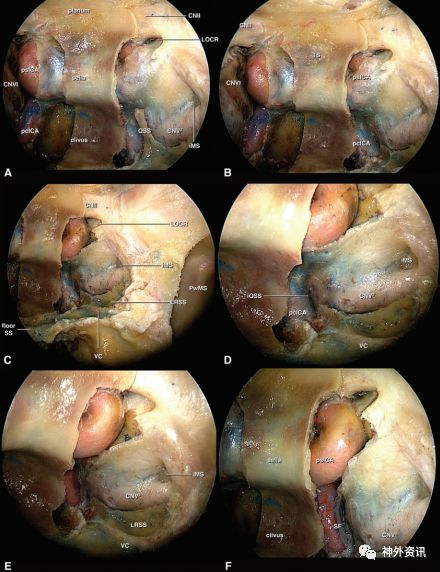

图1. EEA使用0度镜(A、B和C)和30度镜(D、E和F)逐步解剖翼腭窝和海绵窦。A.辨认颅底外科手术中的重要解剖标志,充分打开上颌窦,暴露上颌窦后壁,在上颌窦后壁后方可见到右眶下动脉及其相应的神经走行于右眶上方。在其上、后方可见到筛骨纸样板,从其内侧、上方至筛骨纸样板称为筛板,位于中线上,是入前颅窝的重要解剖标志。在上颌窦后壁的后、下方至筛板有鞍区和斜坡两个重要的解剖标志;B.暴露蝶腭孔,其内有鼻中隔动脉经过,供应鼻中隔,是一个重要的识别标志。从蝶腭孔的下方和内侧至蝶腭孔处为咽鼓管;C.蝶腭孔和眶下神经及其上颌窦后壁对应动脉的近面观;D.切除上颌窦后壁骨质,进入翼腭窝;E.切断位于翼腭窝内的上颌动脉供应骨和骨膜分支,从外侧至翼腭窝为颞下窝。颈外动脉的主要分支为上颌动脉,对颅底外科手术来说,最重要的是蝶腭动脉;其他的分支有腭大动脉和上牙槽后动脉;F.分离海绵窦外侧壁和QS,翼管神经贯穿其中,起于翼腭神经节止于破裂孔;海绵窦外侧壁有Ⅲ、Ⅴ1、Ⅴ2和Ⅵ颅神经;从破裂孔向颅内段暴露ICA,便可观察到QS的边界。

图2. 使用0度镜(A、B和F)和30度镜(C、D和E)观察QS及其周围结构。A.切除蝶窦后壁左、右两侧骨质和右侧硬膜,可见到ICA斜坡段和鞍旁段;保留左侧硬膜完整,向上外侧看到视神经颈内动脉隐窝,这是视神经和ICA之间重要解剖标志;下方,从外到内,可见到位于硬膜后的上颌柱压迹和上颌神经,保留QS前方骨质,这部分成为QS柱;B.切除QS柱;C.30度镜下,可见到整个翼管神经走行于翼管内,可见到位于翼管神经和上颌神经之间的蝶窦外侧隐窝;切除视神经颈内动脉外侧隐窝周围硬膜,显示鞍旁段ICA与视神经的毗邻关系;D.30度镜进一步显示硬膜内的QS压迹;E.切除斜坡段ICA周围的硬膜,翼管、蝶窦外侧隐窝和上颌神经压迹的近面观;F.进一步显示QS周围结构,可见沿ICA斜坡段走行的神经。